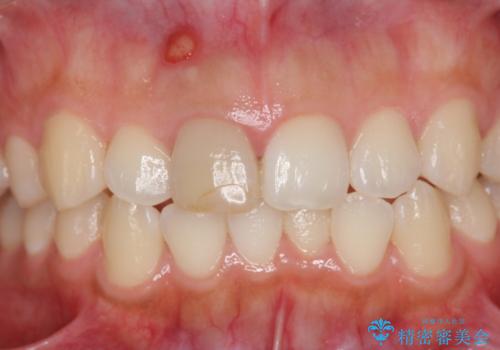

歯ぐきにできものができた 前歯の色調改善

- 歯ぐきに、にきびのようなものができ治らない、と治療を希望され来院されました。

歯髄の検査、X線検査より神経の失活が確認されたので、根管治療・ファイバーコア築盛 ・ジルコニアクラウンの製作、と治療を進めます。